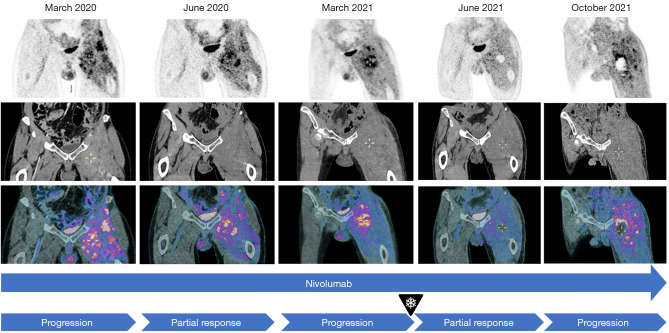

背景:转移性低分化脂肪肉瘤(DDLPS)主要采用化疗,但反应率较低。放疗和经皮冷冻消融等局部疗法可缓解无法手术的转移性肉瘤。在极少数情况下,这些消融疗法可使未经治疗的转移瘤在免疫介导下消退,这一过程被称为 "腹水效应"(abscopal effect)。随着免疫疗法的应用越来越广泛,近十年来关于腹水效应的报道也越来越频繁:病例描述:一名 55 岁的患者被诊断为 DDLPS IV 期,既往无病史。患者首先接受了诱导化疗,随后接受了整体切除术和辅助放疗。经过两次局部化疗复发后,患者出现了全身性疾病进展。在接受免疫化疗的同时,患者接受了姑息性经皮冷冻消融术。术后三个月,18氟脱氧葡萄糖正电子发射断层扫描/计算机断层扫描(18FDG PET/CT)显示,在冷冻消融肿瘤消退的同时,远处转移灶也出现了消退,这表明存在缺席效应:结论:在疾病进展后出现腹膜后效应,表明冷冻消融引发了全身免疫反应,凸显了这种治疗组合的潜力。然而,这仍是一种罕见现象,需要进一步研究和临床试验来确定最佳治疗顺序。

Case description: A 55-year-old patient with no prior medical history was diagnosed with a stage IV DDLPS. The patient was first treated with induction chemotherapy followed by en bloc resection and adjuvant radiotherapy. After two local relapses treated with chemotherapy, the patient developed a systemic disease progression. While progressing on immunochemotherapy, the patient underwent palliative percutaneous cryoablation. Three months after the procedure, the 18fluorodeoxyglucose positron emission tomography/computed tomography (18FDG PET/CT) showed regression of the distant metastasis alongside the regression of the cryoablated tumor, suggesting an abscopal effect.

Conclusions: The occurrence of the abscopal effect after progressive disease suggests that cryoablation triggered a systemic immune response, highlighting the potential of this treatment combination. However, it remains a rare phenomenon, and further research and clinical trials are required to determine optimal treatment sequencing.